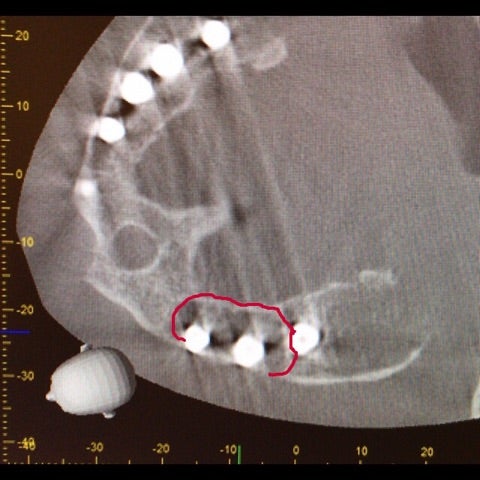

3次元的に精査する必要もある状態であったためCT撮影も行いました。

<CT画像>

▶︎CTからもインプラントを取り囲む顎骨の吸収が確認できました。

重度インプラント周囲炎の診断の下、インプラント除去手術を行う事となりました。